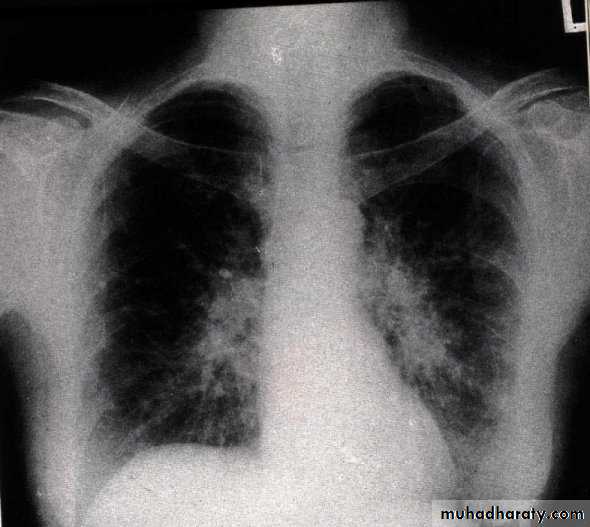

Diffuse Interstitial Disease

Spectrum of diseases that involves pulmonary connective tissue .Many of the diseases have a similar clinical picture and an unknown etiology

Present with dyspnea, tachypnea, crackles, cyanosis, and wheezing. Pulmonary function tests show decreased diffusing capacity, lung capacity, and compliance

Chest x-ray shows irregular lines or a ground glass appearance

Eventual pulmonary hypertension, cor pulmonale, and honeycomb lung occur.